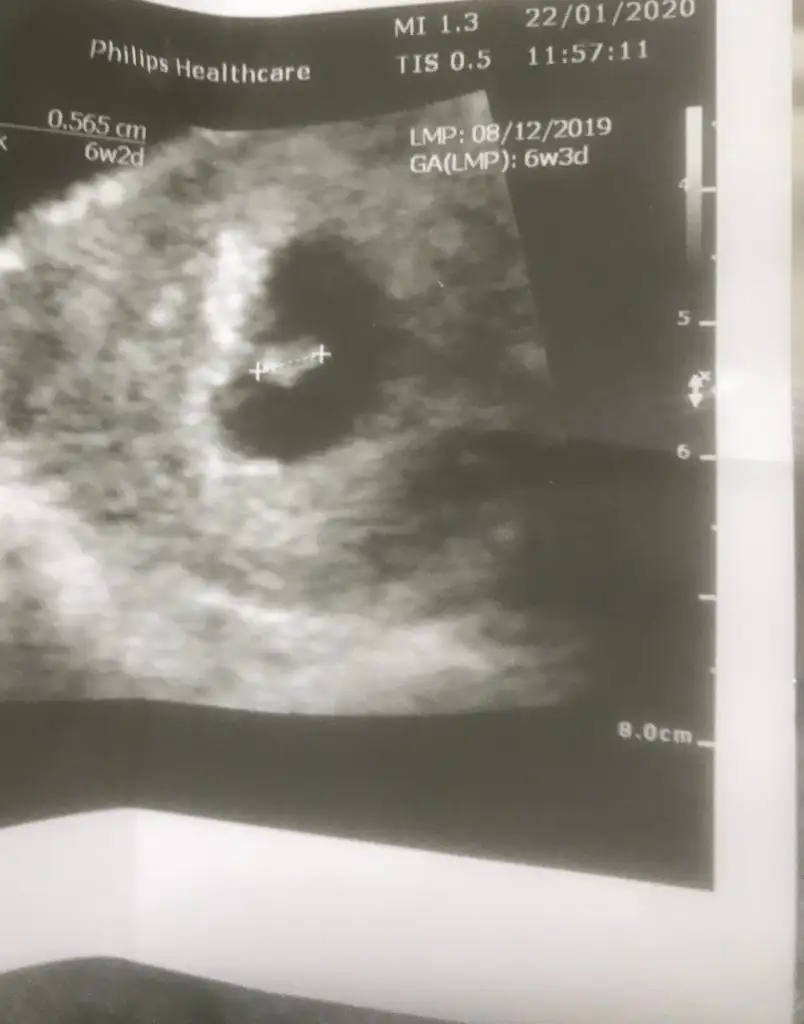

Ben de bugün gördüm sonunda bebişimi çok şükür.. 6+2 deyiz 5mm miş şuan. Kalp atışını duyamadık ama gördük pıt pıt atıyodu minicik :)